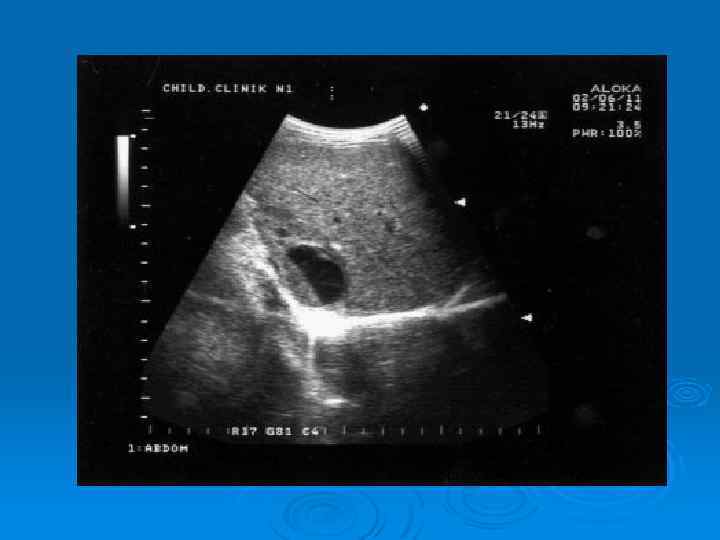

Утолщение стенки лоханки при остром пиелонефрите

Абсцесс верхнего полюса почки у ребенка, 11 лет